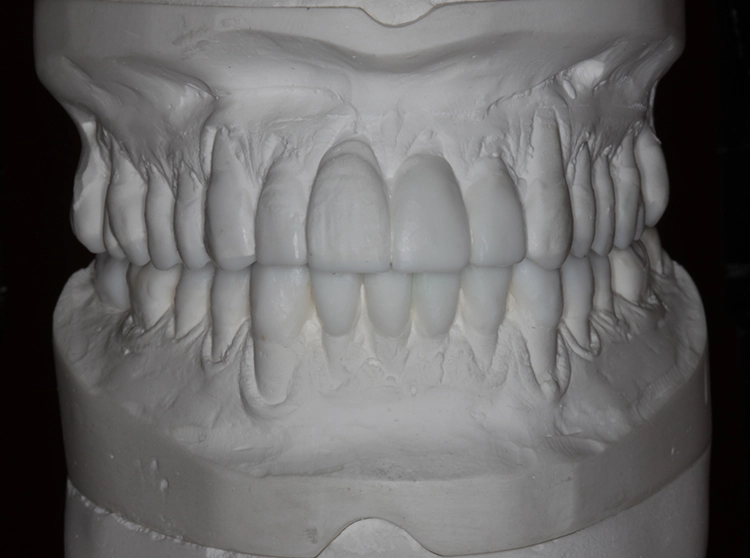

Als erstes sollte eine Dentalhygiene durchgeführt werden mit Abformung für Situationsmodelle, Total Wax-up, Fotostatus, Bissnahme in zentrischer Kondylenposition (ZKP) und Gesichtsbogenübertragung. Dann sollten eine konservierende Versorgung der kariösen Läsion am Zahn 42 mit Komposit sowie eine Wurzelbehandlung am Zahn 46 erfolgen.

Es wurde die Etablierung einer neuen vertikalen und horizontalen Relation des Unterkiefers in zentraler Kondylenposition (ZKP) mit temporären Kompositaufbauten von 17–27 im Oberkiefer und 37–47 im Unterkiefer auf Basis des Wax-up mittels transparenter Silikonschlüssel (Elite Transparent, Zhermack) direkt im Mund des Patienten durchgeführt. Bei der Reevaluation nach der Adaptationsphase von 2 Monaten schienen sämtliche für die definitive Versorgung vorgesehenen Zähne sicher erhaltungswürdig. Der Patient fühlte sich mit der neuen horizontalen und vertikalen Bisslage sehr wohl, und es lagen keine Anzeichen oder Symptome einer Kiefergelenkdysfunktion vor.

Im Rahmen einer Prophylaxesitzung erfolgte eine Reevaluation, und es wurden eine professionelle Zahnreinigung durchgeführt, die Abformung OK/UK mit Alginat vorgenommen sowie der Fotostatus und ein Wax-up erstellt (Abb. 10). Die kariöse Läsion 42 wurde mit Komposit unter Kofferdam konservierend versorgt (Syntac Adhäsiv, Tetric Evo Ceram, Vivadent). Ebenso erfolgten eine endodontische Versorgung 46 nach vorangegangenen pulpitischen Beschwerden sowie die maschinelle Aufbereitung mit NiTi-Feilen (MTWO, VDW) sowie die Wurzelfüllung mit Guttapercha und Sealer (AH Plus, Dentsply) mit lateraler Kondensationstechnik.

Eine neue vertikale und horizontale Relation des Unterkiefers in zentrischer Kondylenposition (ZKP) wurde mit temporären Kompositaufbauten von 17–27 im OK/UK (Tetric Evo Ceram, Vivadent) auf Basis des Wax-up mittels transparenter Silikonschlüssel (Elite Transparent, Zhermack) direkt im Mund des Patienten und unter Zuhilfenahme einer Lupenbrille (4,5-fache Vergrößerung, Zeiss) etabliert. Für das Auffüllen der transluzenten Schlüssel wurde vorgewärmtes Komposit verwendet, um Verzerrungen zu vermeiden. Beim Aufsetzen des Schlüssels auf die zuvor konditionierte Zahnoberfläche wurde die Lichtpolymerisation direkt durch den Schlüssel vorgenommen (Abb. 11).